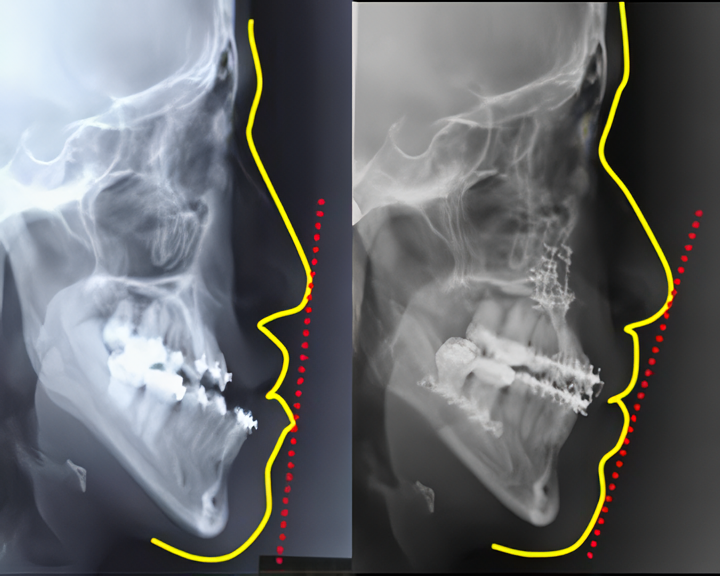

顎変形症:受け口や出っ歯の高度な治療

顎変形症は、上顎骨や下顎骨の過成長や劣成長などによって咬み合わせの異常や顔貌の不調和を引き起こす疾患です。咬み合わせの問題は、発音障害や精神的な悩みの原因となることもあり、患者様の生活の質に大きな影響を及ぼします。原因は遺伝的要因だけでなく、先天的な疾患や腫瘍、外傷によるものなど多岐にわたります。

大阪けいさつ病院では、矯正専門医による診断のもと、外科矯正手術の適応を慎重に判断しています。手術は全身麻酔下で行い、成長が終了した時期(17~20歳以降)に実施します。術前には矯正治療を行い、手術後の理想的な咬み合わせに合わせて歯並びを調整します。手術では、上顎や下顎、または両方の骨を分割して適切な位置に移動し、ネジやプレートで固定します。すべての操作は口腔内から行うため、顔の表面に傷が残る心配はありません。

術後は一定期間、顎間固定を行い咬み合わせの安定を図ります。退院後も定期的な通院と矯正治療を継続し、最終的な咬合の安定と機能回復に努めています。